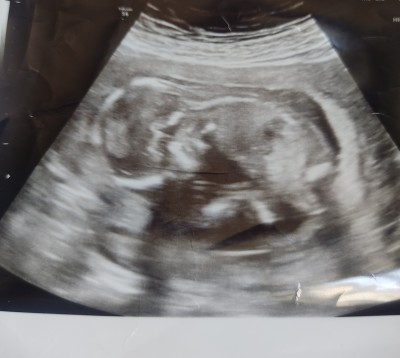

Bebeğime bir doktor erkek dedi farklı doktor kız dedi eşim ailenin tek çocuğu Rabbimden gönlümüzden geçeni istiyoruz hayirlsii ile İnslah verir ama doktor kesin birşey demedi sizce ne olabilir tahmin yürütebilen annelerimiz var mı

Ultrason görüntüsü benimkine benziyor kız dedi doktor bana ne yalan diyim içimden de kız geçti sağlıkla al kucağına canim

Bacak arasi bos canim %99 kiz .

Erkek olan bebege farkli bir doktor bile olsa kiz demez zaten :)

Erkek diyen doktor kendi özel doktorum pozisyonundan dolayı çok göremedi bacak arası ni ayakları çapraz gibiydi kız diyen ise devlet doktoruydu cihazı çok eskiydi canımı çok acitmisti

Bende kız dedim ama hata bana göre kesin kız dedim ama sana göre neden kesin kız diye sordu arkadaş. Bacakları capraz bile olsa testisleri görünür bebeğin. Bende aynı şey oldu. Ama Rabbim gönlündekini nasip etsin sağlık sıhhatle

Benim oğlanın da var böyle bir ultrason görüntüsü , tavşan gibi (siyah beyaz) :)) sağlıkla gelsin inşallah ♥️